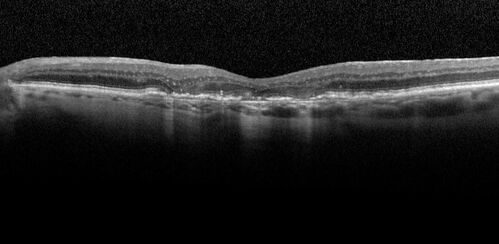

Pigment migration in dry age-related macular degeneration

80 year old female. Dry AMD with GA in the left eye and pigment migration visible on OCT scan.

VA 20/40 OD, 20/160 OS